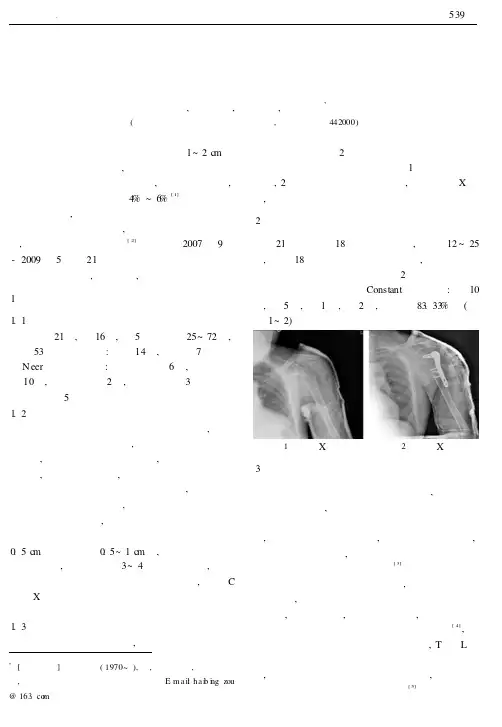

我院自2007年9月-2009年5月对21例肱骨近端骨折患者采用锁定接骨板内固定治疗,效果满意,报道如下。

1临床资料1.1一般资料本组21例,男16例,女5例。

年龄25~72岁,平均53岁。

致伤原因:摔伤14例,车祸伤7例。

根据N eer 骨折分型标准:一部分骨折6例,二部分骨折10例,三部分骨折2例,四部分骨折3例。

合并肩关节脱位5例。

肱骨近端锁定接骨板安置在肱骨大结节顶点下0.5c m 、结节间沟后0.5~1c m 处,安装导向装置及钻头导向器,肱骨头采用3~4枚锁定钉固定,骨折远侧端采用锁定钉结合普通加压螺钉固定,术中C 形臂X 线机透视证实骨折端复位满意、锁定接骨板安置无误后逐层关闭切口。